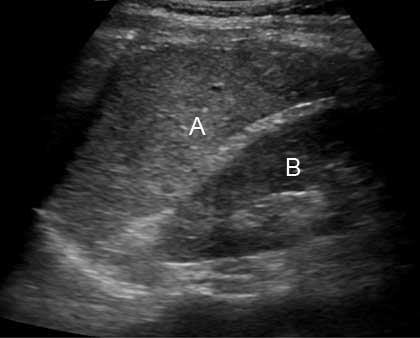

Ultrasonido del bazo y riñón izquierdo— Paciente boca arriba con la cabeza a la izquierda

a. bazo

b. riñón izquierdo